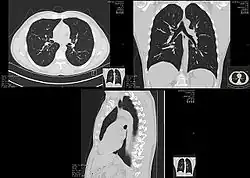

.jpg)

Different types of diseases or conditions that affect the chest include pleurisy, flail chest, atelectasis, and the most common condition, chest pain. These conditions can be hereditary or caused by birth defects or trauma. Any condition that lowers the ability to either breathe deeply or to cough is considered a chest disease or condition.

The major pathophysiologies encountered in blunt chest trauma involve derangements in the flow of air, blood, or both in combination. Sepsis due to leakage of alimentary tract contents, as in esophageal perforations, also must be considered. Blunt trauma commonly results in chest wall injuries (e.g., rib fractures). The pain associated with these injuries can make breathing difficult, and this may compromise ventilation. Direct lung injuries, such as pulmonary contusions (see the image below), are frequently associated with major chest trauma and may impair ventilation by a similar mechanism.